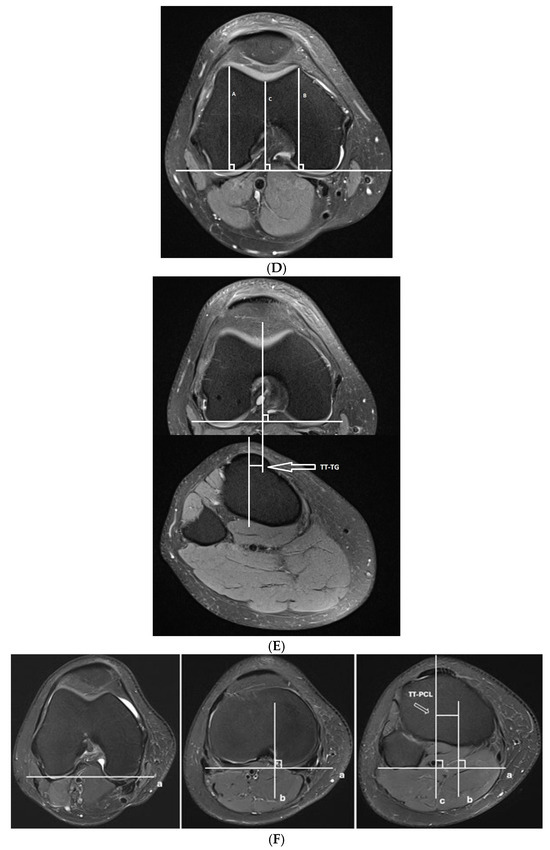

- Trochlear dysplasia measurements